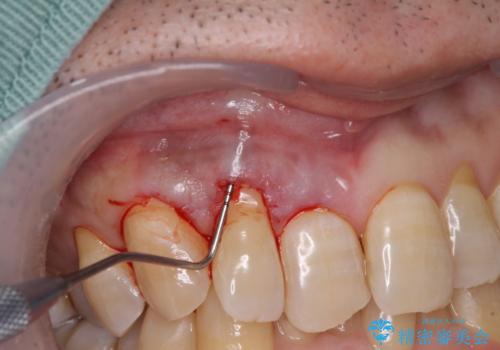

- 強い咬合力による歯肉退縮により、歯の根の黄色い色が見えてしまうことを気にされて来院された患者様です。

口蓋(上顎の内側)から採取した結合組織(歯肉の内側の組織)を移植することによる、根面被覆術を行うこととしました。

ディープバイトで咬合力が強く、該当歯に負担のかかりやすい咬み合わせであったため、歯肉退縮が起こりやすいと判断された患者様でした。

根面被覆を達成するとともに、歯肉の厚みを増すことで、今後歯肉退縮を起こしにくくするよう配慮した処置としました。